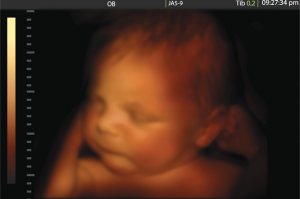

Utilizzando invece metodiche 3D e 4D, l’ecografo memorizza un numero di sezioni effettuando il cosiddetto “rendering tridimensionale”, un’immagine estremamente accurata e molto simile al vero.

In ostetricia è possibile dunque ottenere delle immagini molto realistiche ed in grado di “catturare” il feto come realmente è, proprio come se scattassimo una fotografia dall’interno del “pancione” della mamma.